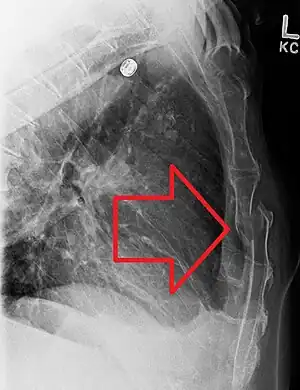

A displaced sternal fracture as seen on plain X-ray

X-rays of the chest are taken in people with chest trauma and symptoms of sternal fractures, and these may be followed by CT scanning.[12] Since X-rays taken from the front may miss the injury, they are taken from the side as well.[13]